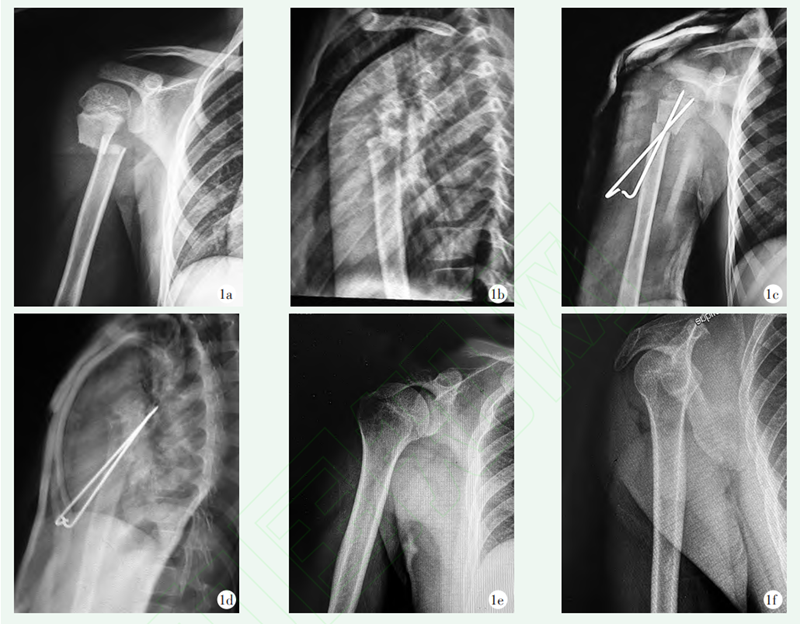

图1 患者,男,12岁,右侧肱骨近端骨折,行闭合复位经皮克氏针固定

1a,1b:术前正侧位X线片示骨折严重移位,为Neer-Horowitz 4型;1c,1d:术后正侧位X线片示骨折对位对线满意;1e,1f:术后5年正侧位X线片示骨折愈合,颈干角恢复并保持满意